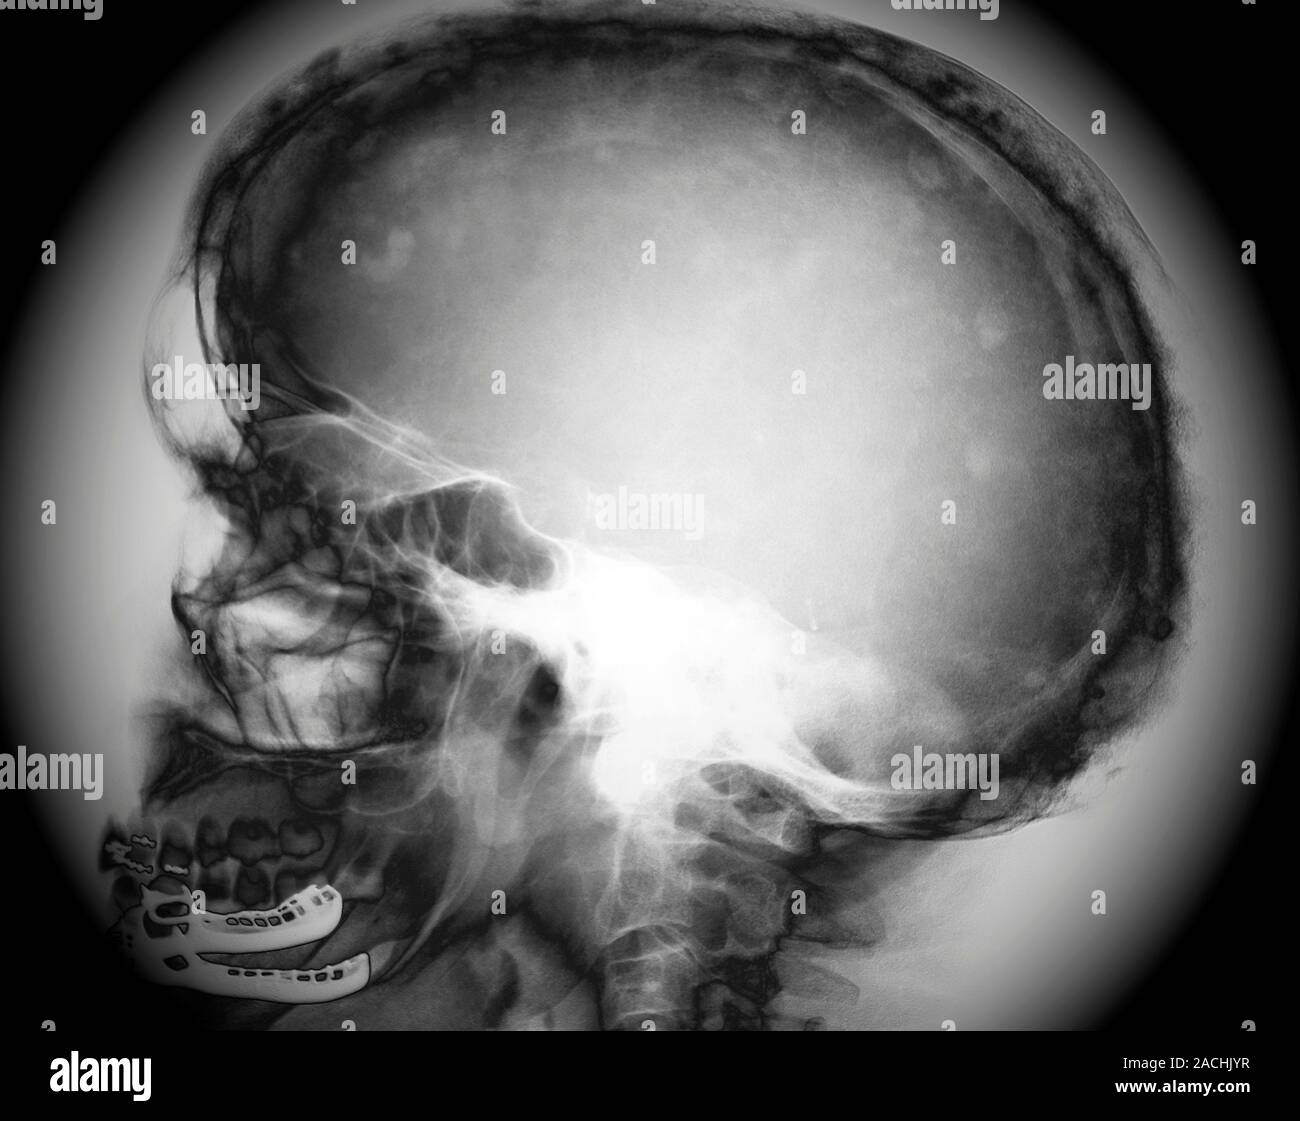

From www.alamy.com

Paget's disease. Lateral Xray of the skull of a 62yearold patient Paget's Disease Also Known As Paget's disease of bone is a chronic bone disorder due to irregular breakdown and formation of bone tissue. Paget’s disease may affect only one bone when it is known as monostotic paget’s disease. Paget disease is a skeletal growth disorder in which abnormalities such as unusual bone growth can occur in several multifactorial. Paget’s disease of the bone is a. Paget's Disease Also Known As.